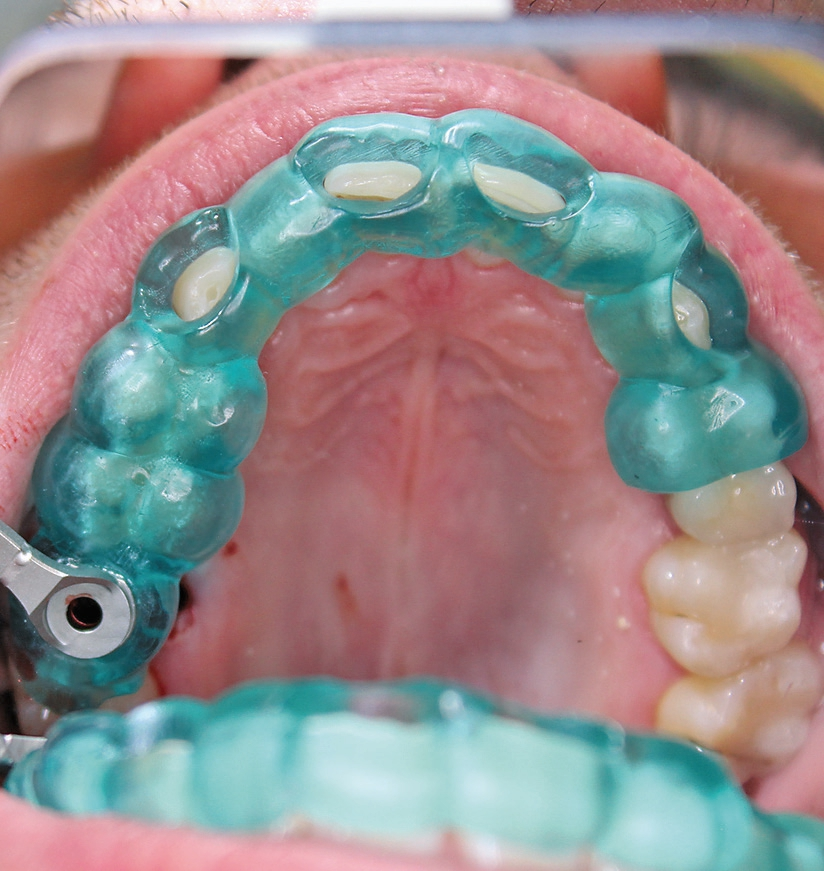

Nach der Präparation des Weichgewebes wurde ein Mukoperiostlappen mit Hilfe der Instrumentenspitze PR2 (Piezosurgery, Mectron, I-Genua) vorsichtig präpariert, um eine suffiziente Deckung der Wunde zu gewährleisten (Abb. 9 und 10). Nach Vorbereitung des Weichgewebes wurde die 3D-gedruckte Bohrschablone auf den Zahnbogen gesetzt und ein Führungsschlüssel mit 2 mm Durchmesser eingesetzt, durch den ein Osteotom einführt wurde, um eine Führung für den nachfolgenden Trepanbohrer in den Knochen kondensierend zu präparieren (Abb. 11). Entlang des Führungskanals wurde das Bett für den allogenen Knochenring (maxgraft bonering; botiss biomaterials GmbH, Berlin) trepaniert (Abb. 12). Der allogene Knochenring wurde extraoral passgenau zugeschnitten und anschließend in die Extrationsalveole platziert (Abb. 13 und 14). Mittels eines breiten Osteotoms wurde der Knochenring samt basalem Knochensegment schablonengestützt nach apikal in den Sinus maxillaris verschoben. Ein parallelwandiges Implantat (Bone Level Roxolid, SLActive, Straumann) mit einem Durchmesser von 4,1 mm und einer Länge von 10 mm wurde zentral in den positionsstabilen Knochenring primärstabil inseriert, mit einer Fixierungkappe (Durchmesser 5,5 mm) versehen und die umliegende Extrationsalveole mit granulärem bovinem Knochenersatzmaterial ausgefüllt (Abb. 15-17). Anschließend wurde die Wunde mit dem Mukoperiostallappen gedeckt und speicheldicht vernäht (Abb. 18). Zur postoperativen Kontrolle wurde ein Orthopantomogramm aufgenommen, auf dem keinerlei Verletzungen benachbarter anatomischer Strukturen zu erkennen sind (Abb. 19). Es folgten zwei radiologische Verlaufskontrollen, vier und sechs Monate nach dem Eingriff, ohne Besonderheiten (Abb. 20 und 21).

Nach einer sechsmonatigen Einheilzeit wurde das Implantat freigelegt und die Fixierungskappe entfernt. Es folgte die handfeste Insertion des Healingabutments. Das Healingabutment wurde für drei Wochen getragen, um das Emergenzprofil zu formen. Nach Ausformung des Emergenzprofils wurde das Healingabutment temporär für die Implantatabformung entfernt und der Abformpfosten eingeschraubt und radiologisch auf Passgenauigkeit kontrolliert (Abb. 22). Die offene Abformung erfolgte mittels individuellem Abformlöffel und Vinyl-Polyether-Silikon. Es wurde eine verschraubbare Krone aus Lithium-Disilikat-Glaskeramik (IPS e-max CAD, Ivoclar Vivadent, FL-Schaan) angefertigt und mit 20 Ncm festgeschraubt. Die Schraube im Schraubenkanal wurde mit einem Schaumstoffpellet isoliert und der Kanal mit niedrig viskösem Kunststoff versiegelt (Abb. 23).